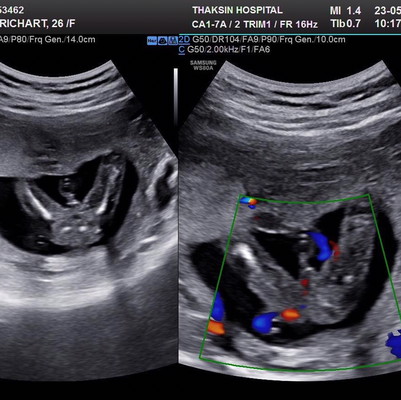

ซาวตอน16วีค ที่เห็นคือจู๋หรือสายสะดือคะ? ความไปได้มากน้อยแค่ไหนที่จะเป็นผู้ชาย? และมีความมากน้อยแค่ไหนที่จะเป็นผู้หญิง? #ตอนซาวหมอไม่ได้บอกค่ะ

สายสะดือภาพขวามือส่วนที่เป็นสีๆอะค่ะ คือเส้นเลือดที่วิ่งอยู่ เราว่าของแม่น่าจะเป็นเด็กผู้ชายน้า เพราะเห็นว่าเป็นจู๋ ไม่ใช่สายสะดือจ้า

ไม่ชัดเจนเท่าไร เพราะสายสะดือพาดกลางพอดีเลยเห็นไม่ชัดว่าจู๋รึป่าวค่ะ หมอเลยไม่ตอบมั้งค่ะ

ไม่แน่ใจค่ะ เหมือนทับซ้อนระหว่างเพศกับสายสะดือ😅😅